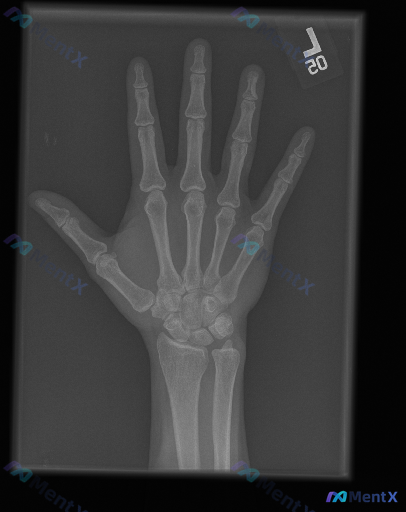

左手正位X光片报告基本正常,但提示存在异常,这种情况更优先考虑哪种方向?

整理到一组影像资料和配套的分析背景,想和大家讨论下这种情况的思路: - 影像来源:左手正位X光片 - 常规阅片所见: - 各腕骨、掌骨、指骨骨皮质轮廓尚完整,未见明显骨折线、脱位或半脱位; - 骨密度、关节间隙未见明显异常; - 关节面、软骨下骨、软组织影也未见明确的典型异常改变(如骨赘、弥漫肿胀、...

整理到一个影像相关的病例情况,想和大家讨论下判断思路: - 影像资料:左手正位X光片 - 读片所见:各指骨、掌骨、腕骨皮质连续,未见明确骨折线、脱位或半脱位;骨小梁清晰,密度均匀,无明显骨质破坏、骨膜反应或异常钙化;各关节间隙对称、宽度正常,关节面光滑,无明显骨赘或侵蚀;周围软组织轮廓自然,未见明显...

整理到一组左手正位X光片的影像评估资料,同时结合了临床场景的提示,想跟大家讨论一下这种情况的判断思路。 影像所见 - 骨皮质连续性:指骨、掌骨及腕骨骨皮质连续,未见明确骨折线、中断或台阶征;第一掌骨基底、第五掌骨颈区域也无异常 - 骨髓腔密度:骨小梁结构清晰,纹理分布均匀,未见局灶性骨质破坏、虫蚀样...